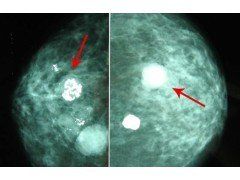

乳房鈣化

早期的乳癌表現可能只是一些散在性鈣化現象,在乳房超音波掃描下僅會呈現一閃一閃的星光現象,需要經驗豐富的醫師或檢驗員才有能力做出判讀;倘若利用乳房X光攝影,則不難清楚看到微小的鈣化點。